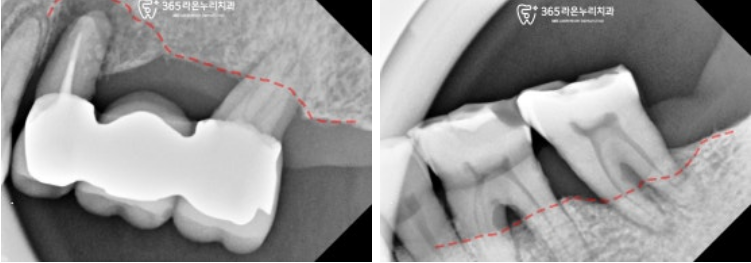

비어있는 오른쪽 아래 구치부도

마찬가지로 살펴보았는데요,

맨 뒤에 임플란트를 심어둔 곳에

염증이 생겨 주변으로 뼈가 녹아있습니다.

■ 3. 식립계획

남촌동 치과 에서는

엑스레이의 정보를 토대로

임플란트 식립 계획을 세웁니다.

환자의 비용적인 측면을 고려하여

상하좌우 각 2개의 픽스처를 심기로 하였으며

(오른쪽 아래 기존 픽스처는 주위염이 생겨

제거 후 다시 심기로 했습니다.)

그 사이에 ponic이라는

인공치를 넣어 저작력을 나눠가질 수 있도록

계획을 짰습니다.